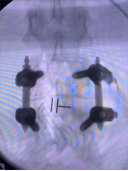

8. 机器人导航辅助下脊柱侧弯矫正技术

脊柱侧弯是一种复杂的脊柱三维畸形,其中以青少年特发性脊柱侧凸最常见。好看视频下载

在浦口地区率先开展机器人导航辅助下脊柱侧弯矫正术,实现了脊柱侧弯手术准确、微创、智能化的突破,获得了良好的效果。还有老年人退变性侧弯,机器人亦可精准置入困难椎弓根螺钉,误差只有0.3mm。